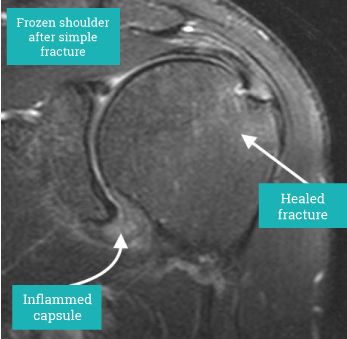

The proximal humerus may fracture into multiple fragments or individual single pieces of bone associated with the attachment of the rotator cuff. Each of these fractures require careful assessment and if displaced surgical management as they are the attachment of the rotator cuff.